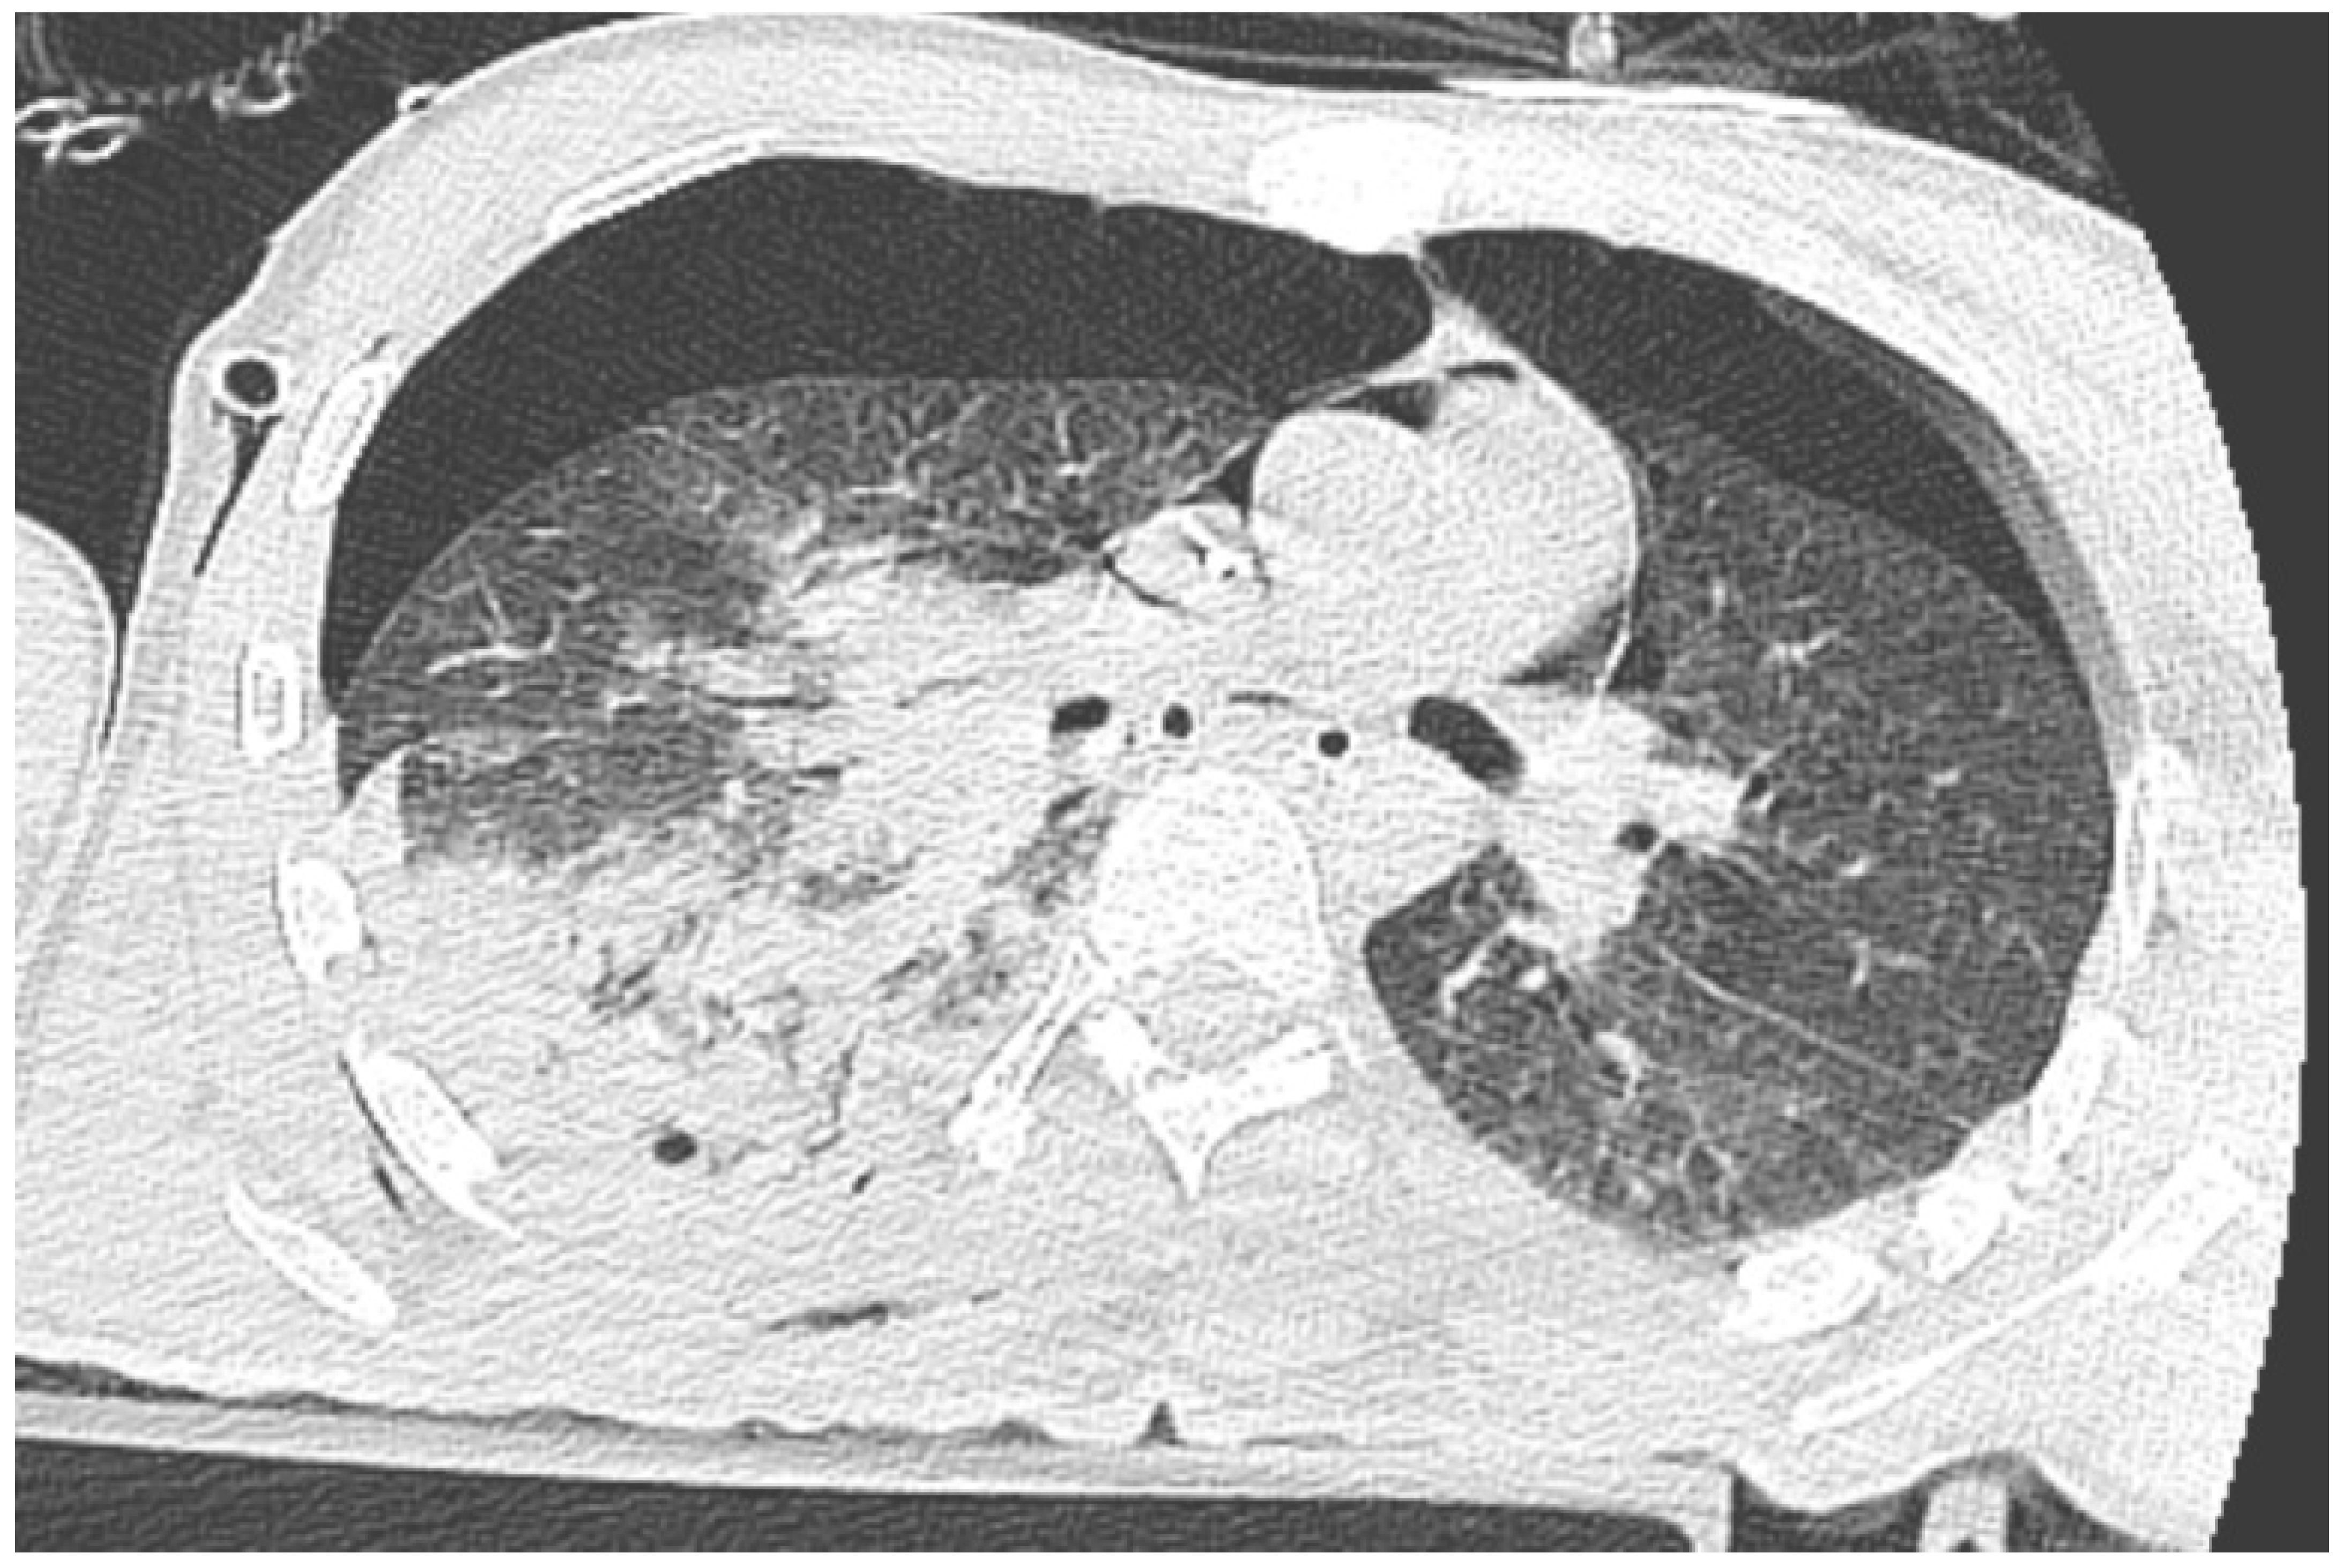

Immediately after decompression, the blood pressure was 134/85 mmHg, the heart rate was 105 bpm, and the saturation was 92%. The critical parameters from the blood gas analyzer just after the decompression of pneumothorax are as follows (11:15 p.m.): pH 7.016, pCO2 45.2 mmHg, pO2 107 mmHg, HCO3 11.6 mmol/L, BE −19.4, anion gap 19.4 mmol/L, and hemoglobin 15.0 g/dL (after transfusion of three units of red blood cells). Laboratory blood tests showed a level of troponin 15,158.657 pg/mL. In the next 30 min, the blood pressure was 85/50 mmHg. Catecholamine infusion was initiated, fluid therapy was continued, and point-of-care ultrasound diagnostics were repeated, Still, we could not obtain the heart from any ultrasound window. A new CT scan was performed with no contrast, and there was bilateral pneumothorax small pneumopericardium in the pericardial cavity (Figure 2 and Figure 3). Drainage of the left pleural cavity was performed. The right drain was oscillating, but it was no longer functional and was trapped in the lung fissure between the expanding lobes of the right lung, which was seen on CT scans. The right pleural drain was replaced, which resulted in an improvement in the patient’s condition. However, he still required the use of catecholamine.

Figure 2. CT scan of pneumothorax and pneumocardium after a pneumopericardial decompression—scan at the level of the diaphragm.